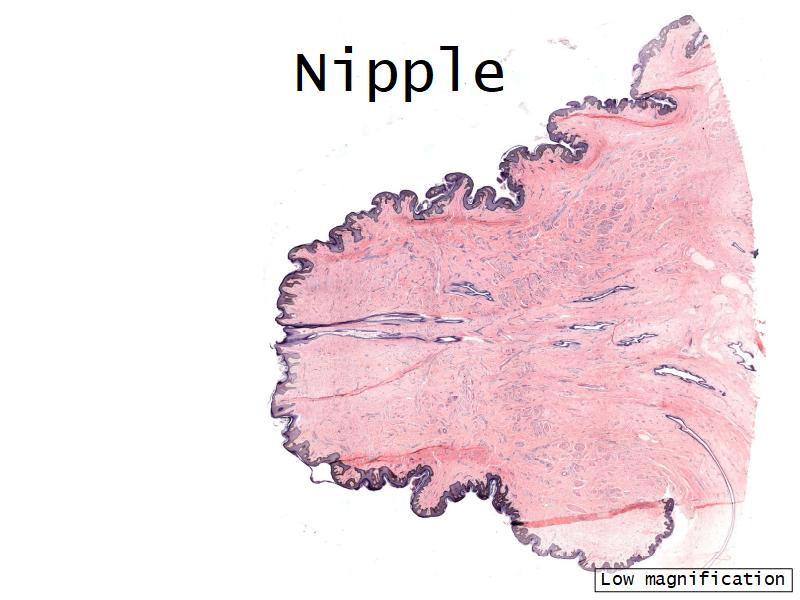

Morphology

What are the main morphological features of the nipple?

(4)

Morphology

- Covered with skin

- Consists of dense collagenous connective tissue

- Interlaced with smooth muscle fibres

- Contains openings of lactiferous ducts

Skin

- Keratinized stratified squamous epithelium

- Sebaceous glands

Stroma

- Collagenous connective tissue

- Irregular dense connective tissue

- Smooth muscle

- Fibres and bundles

- Lactiferous sinusses

- Stratified cuboidal epithelium